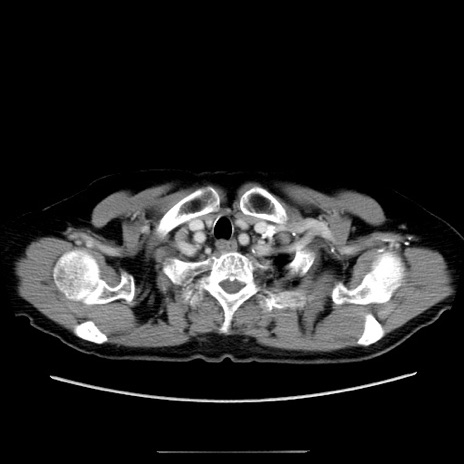

冠状断像

【症例】70歳代女性

【主訴】お腹が張る

【現病歴】1週間くらい前から腹部膨満の自覚あり。昨日夜から増悪したため、本日救急外来受診。

【身体所見】意識清明、BT 36.5℃、BP 165/106mmHg、HR 80bpm、SpO2 98%、腹部:膨満、軟、自発痛・圧痛なし、触診にて不快感あり、腸蠕動音:減弱

【データ】WBC 12600、CRP 1.04